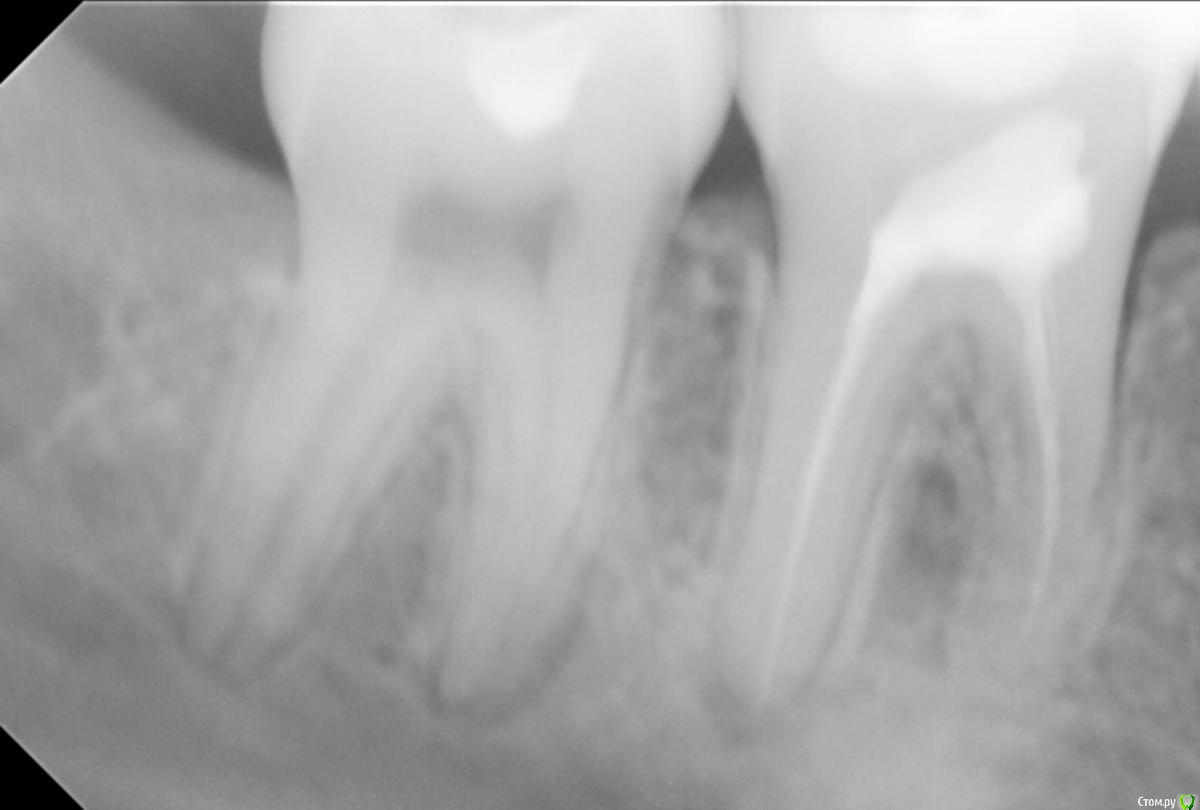

Madness88755 Опубликовано 25 сентября, 2019 Поделиться Опубликовано 25 сентября, 2019 Здравствуйте. Мне 22 года. С августа месяца 2019 года начал беспокоить депульпированный зуб (нерв был удален почти 4 года назад). Боли постоянные, ноющие. Будто болит где-то в кости. Сразу же обратилась к стоматологу. Прочистили каналы, поставили лечебную пасту и временную пломбу. Через три дня пришла снова, так как боли были невыносимые. Прочистили, решили вывести лекарство с кальцием за верхушку корня и поставили временную пломбу. Через неделю поставили постоянную. Боли не беспокоили.2 сентября 2019 года обратилась снова к стоматологу из-за постоянной ноющей боли в зубе. Распломбировали и поставили лекарство с временной пломбой. Сказали придти через 2 недели, но так как стоматолог попала в больницу, попала к ней через 3 недели. Первые две недели все было отлично, боли прошли, но на третью неделю вновь начали усиливаться. Была у стоматолога 23 сентября 2019 года. Почистили каналы и снова поставили лекарство с йодом и кальцием + временная пломба. Через неделю сказала, будем ставить постоянную пломбу и после посоветовала походить на процедуры в стоматологическую поликлинику.Снимок был сделан в июле месяце. Тогда зуб никак не беспокоил, к лечению, как я писала выше, приступили в августе месяце. Стоматолог посоветовала пропить кальций-Д3 НИКОМЕД, что мной и было сделано. Улучшений никаких замечено не было. Прошу разъяснить мне в чем может быть причина болей и что можно сделать в моем случае? Заранее большое Вам спасибо! Ссылка на комментарий

red_butler Опубликовано 26 сентября, 2019 Поделиться Опубликовано 26 сентября, 2019 Покажите актуальный снимок Ссылка на комментарий